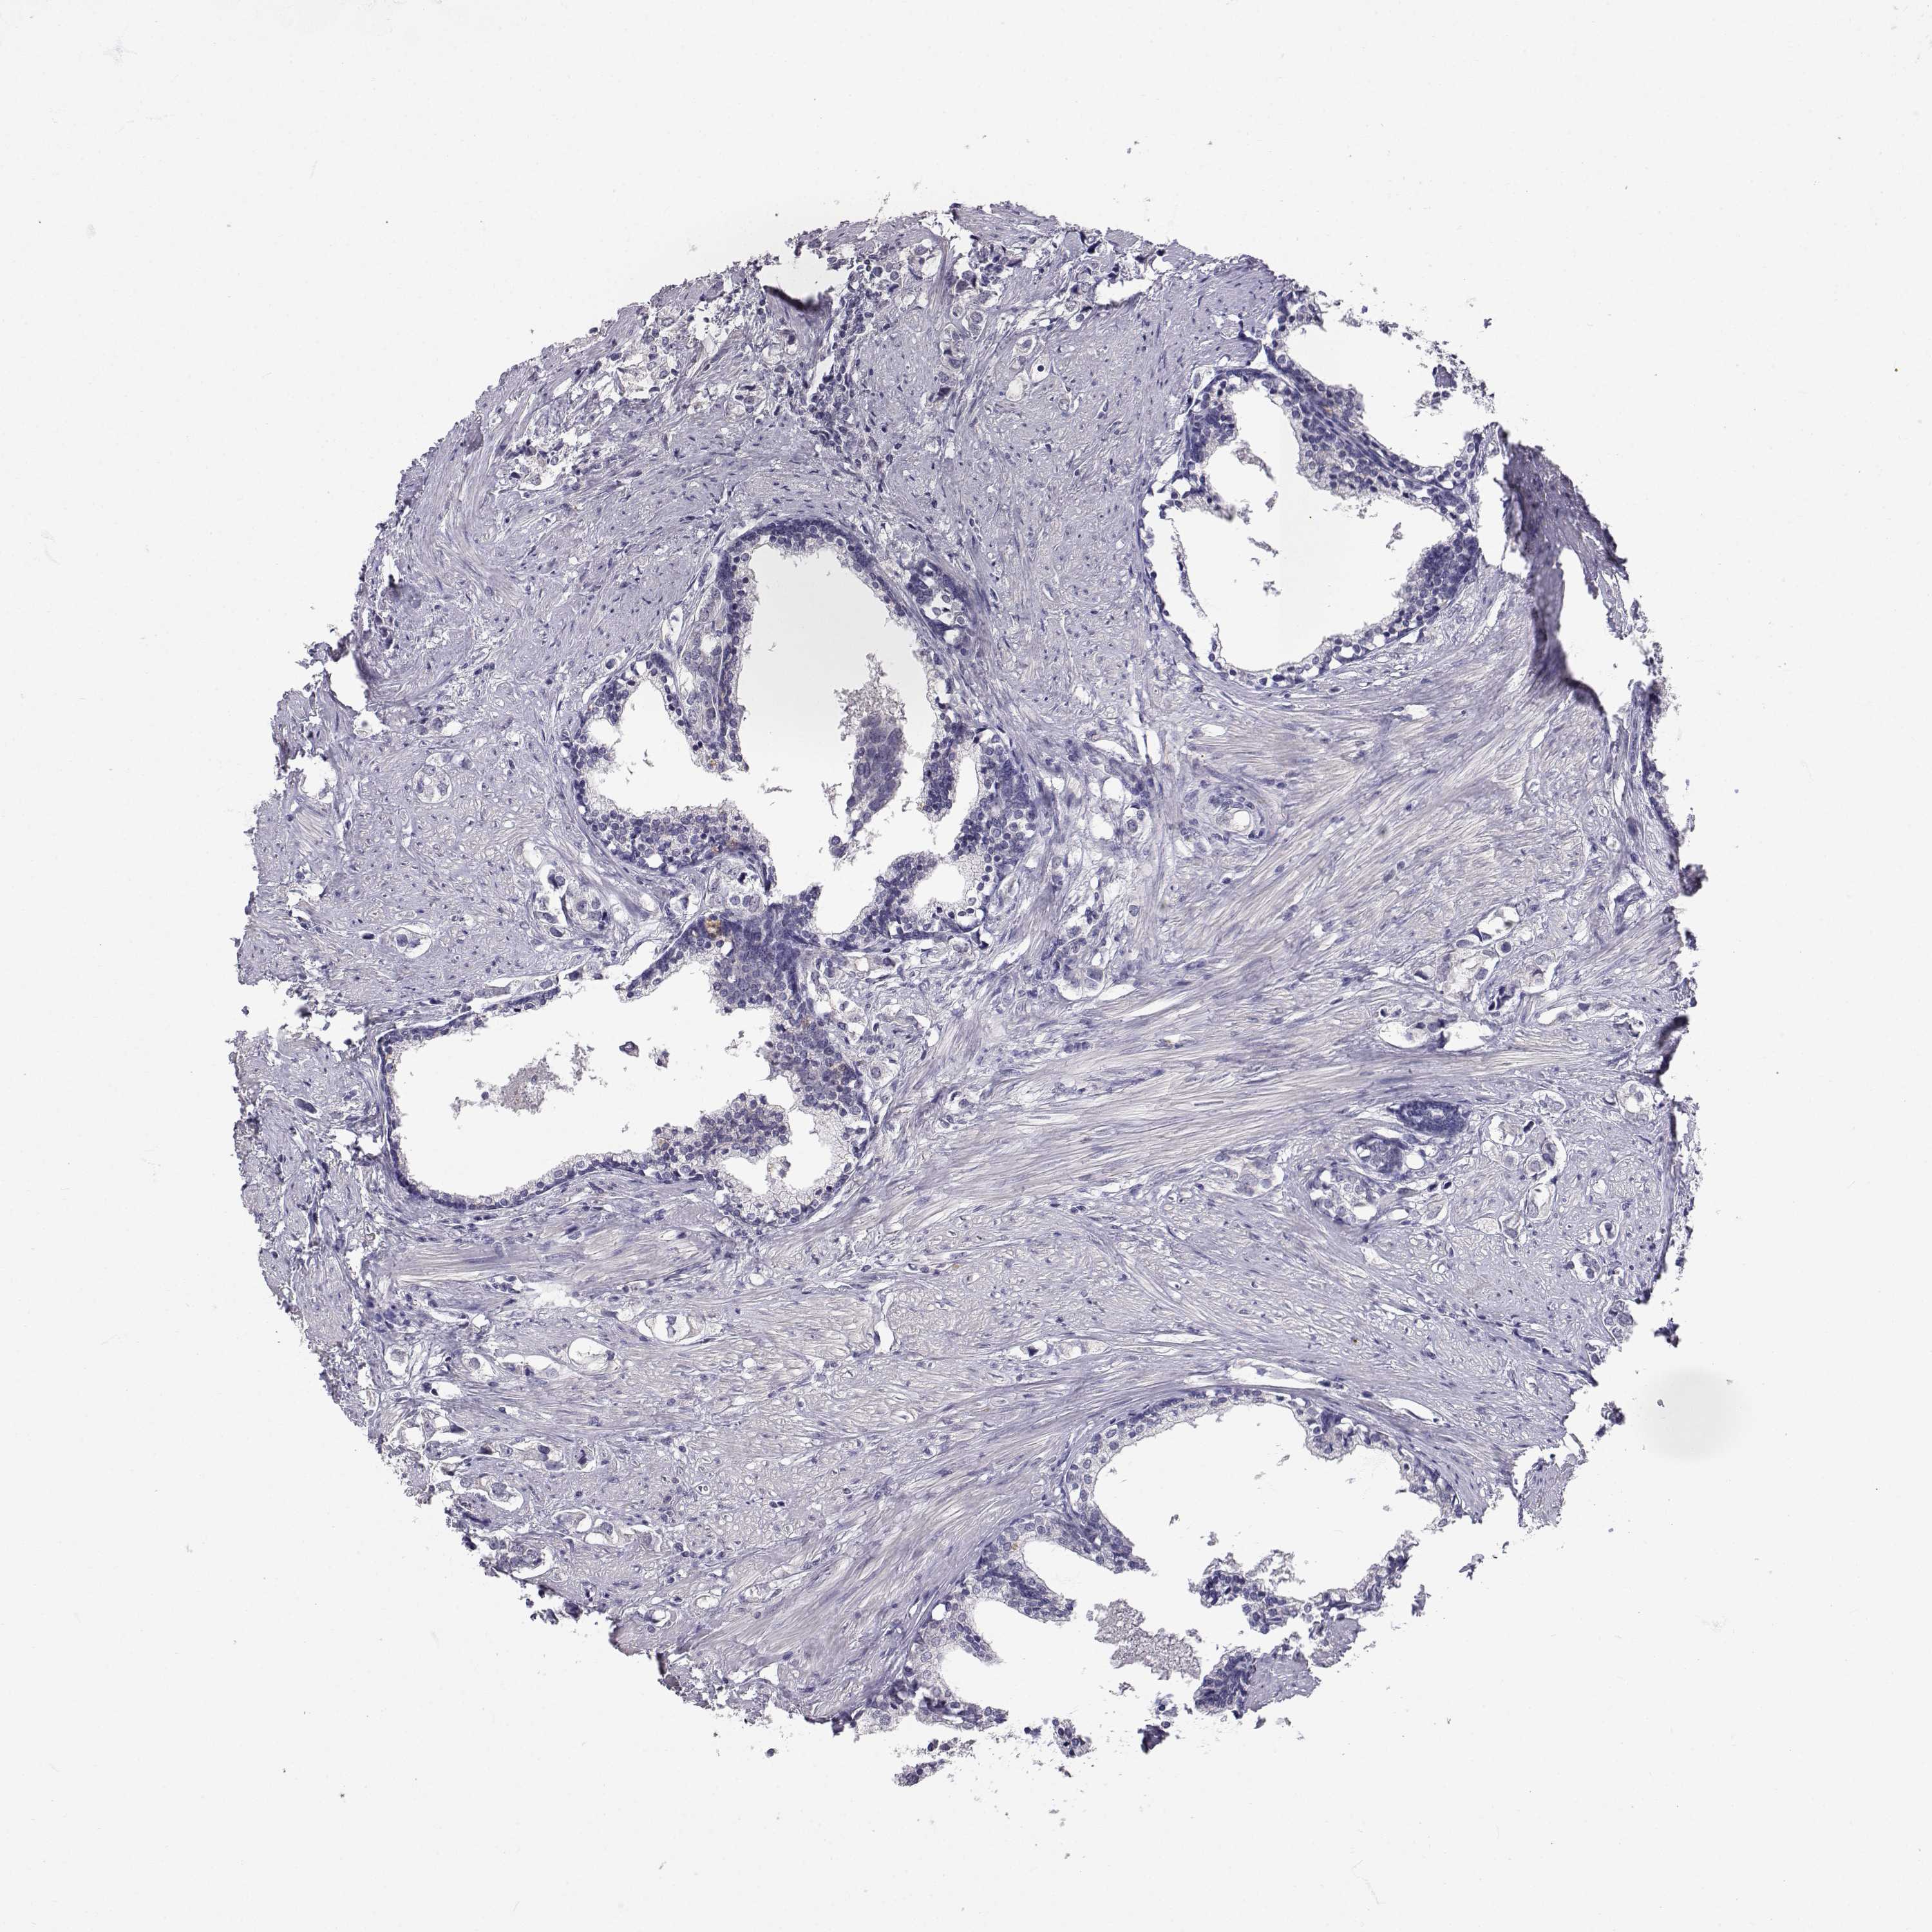

PROSTATE CANCER - Protein expressioni

A mouse-over function shows sample information and annotation data. Click on an image to view it in a full screen mode. Samples can be filtered based on level of antibody staining by selecting one or several of the following categories: high, medium, low and not detected. The assay and annotation is described here.

Antibody stainingi

Antibody staining in the annotated cell types in the current human tissue is reported as not detected, low, medium, or high, based on conventional immunohistochemistry profiling in selected tissues. This score is based on the combination of the staining intensity and fraction of stained cells.

Each image is clickable and will lead to virtual microscopy that enables deeper exploration of all samples and also displays staining intensity scores, fraction scores and subcellular localization as well as patient and tissue information for each sample.

Antibody HPA012763

Adenocarcinoma, Medium grade